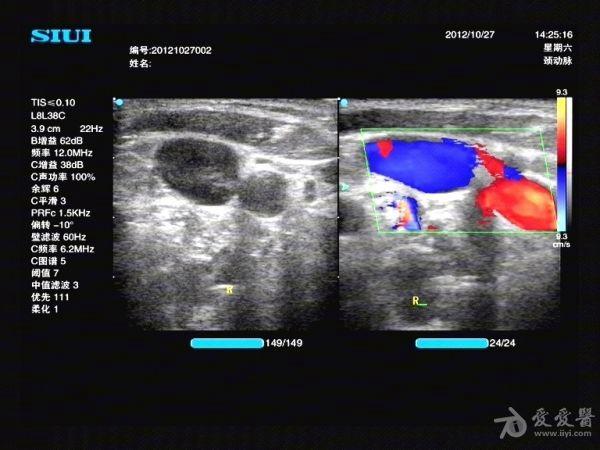

一例颈内静脉血栓-第一次误诊?第二次诊断准确?供大家参考